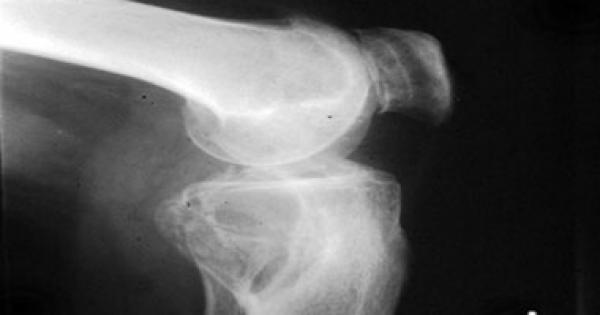

وأشارت الدراسة التى أجراها باحثو جامعة نورث كارولينا إلى أن نقص مستويات فيتامين "د" يزيد من حدة خشونة الركبة، ويرفع من معاناة المرضى ويزيد من حدة آلالامهم، ويظهر التأثير بشكل أكبر على الأشخاص ذوى البشرة السمراء.

ويعانى مرضى خشونة المفاصل من وجود تورم مؤلم وتصلب بالمفاصل، ومن أهمها مفصل الركبة والورك والأصابع، وأصيب بهذا المرض حوالى 25 مليون مواطن أمريكى منذ عام 1980 وحتى 2005 حسب إحصاءات رسمية، وأشار الباحثون إلى أن احتمالات إصابة المواطنين الأمريكيين بخشونة الركبة قد تصل إلى 46%.